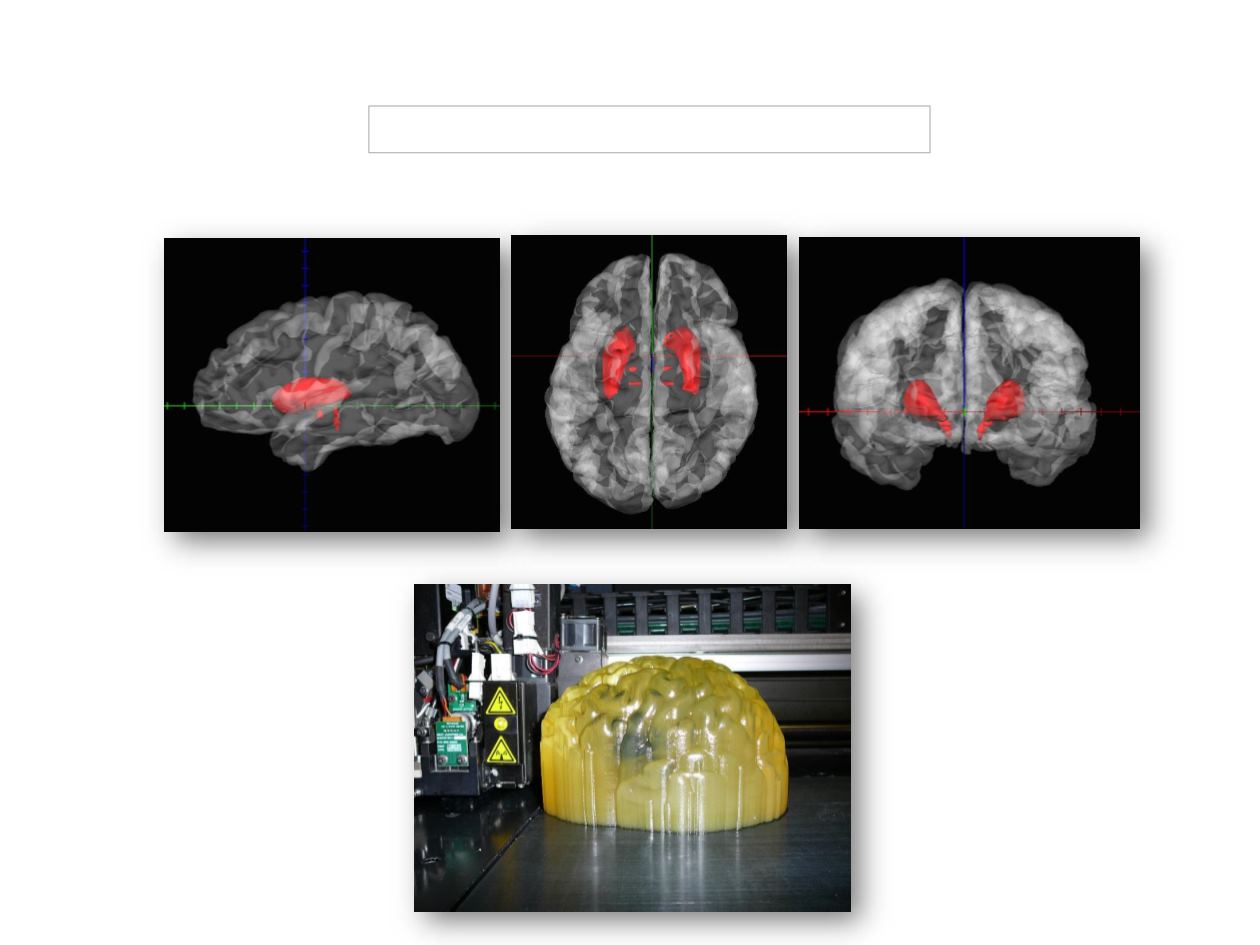

3 D BRAIN PRINTING FOR NEUROMODULATION